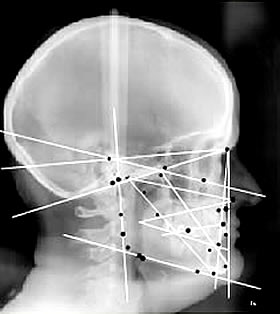

Je suis technicien en prothèse dentaire, spécialisé en occlusion dentaire par analyse céphalométrique

analyse céphalométrique pour déterminer la bonne posture

1992, je découvre l'analyse céphalométrique

A ce moment, je comprends l'importance de l'équilibre du trio crânien (mandibule, crâne et cervicales). Ce trio fonctionne obligatoirement avec le trio bassin.